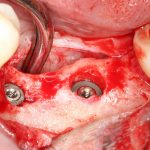

Рекомендации по установке имплантов. Для всех. Часть V.